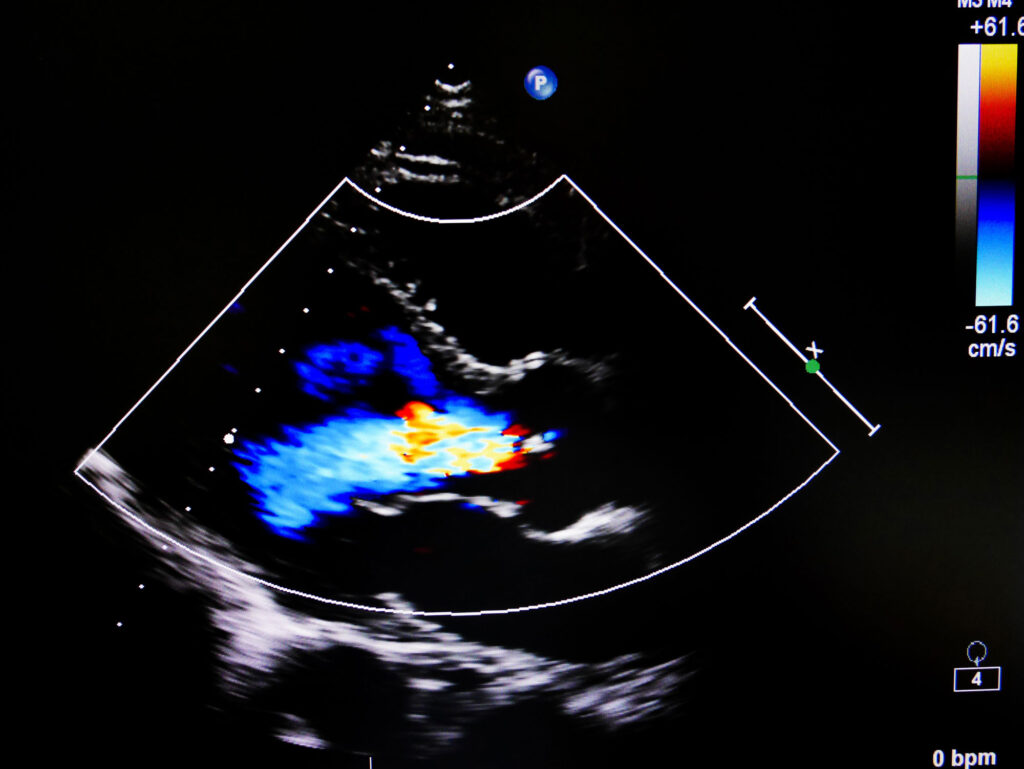

Un ecocardiograma bidimensional (ecografía) permite capturar imágenes del corazón de forma no invasiva mediante ondas sonoras. Esta prueba rutinaria permite al médico examinar la estructura y la función de bombeo del corazón. El médico podrá examinar las válvulas del corazón, el tamaño de las cavidades cardíacas, la velocidad y la dirección del flujo sanguíneo, e identificar cualquier posible anomalía.

Se acostará en una camilla para que un ecografista cualificado le tome imágenes del corazón. Esto se realizará acostándose sobre el lado izquierdo y colocando una sonda en varias partes del pecho. Las imágenes tomadas determinarán la función de bombeo y la estructura general del corazón.